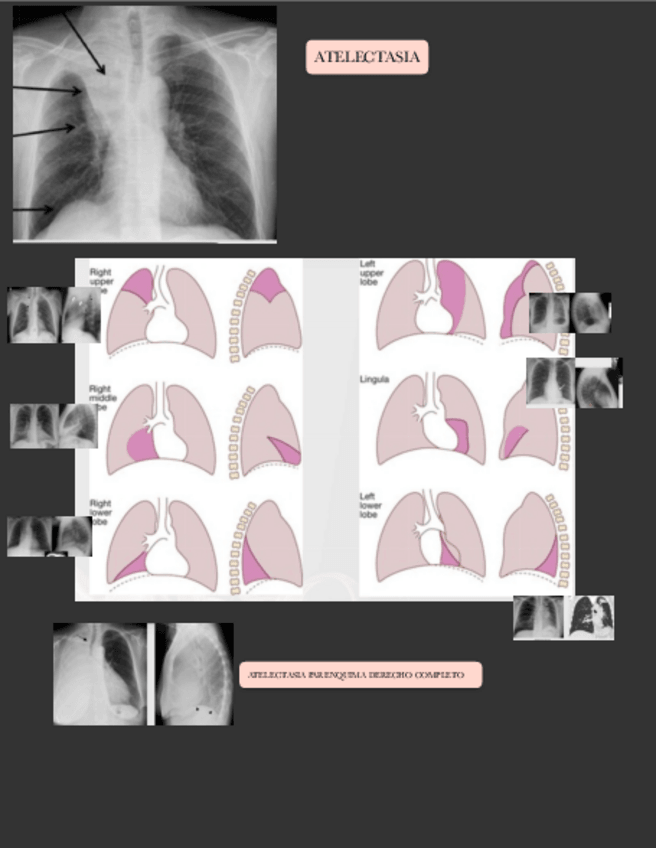

He publicado nuevos apuntes de 3º Radiología y Medicina Física. Protección Radiológica: IMAGENES-RAYOS-TORAX.pdf